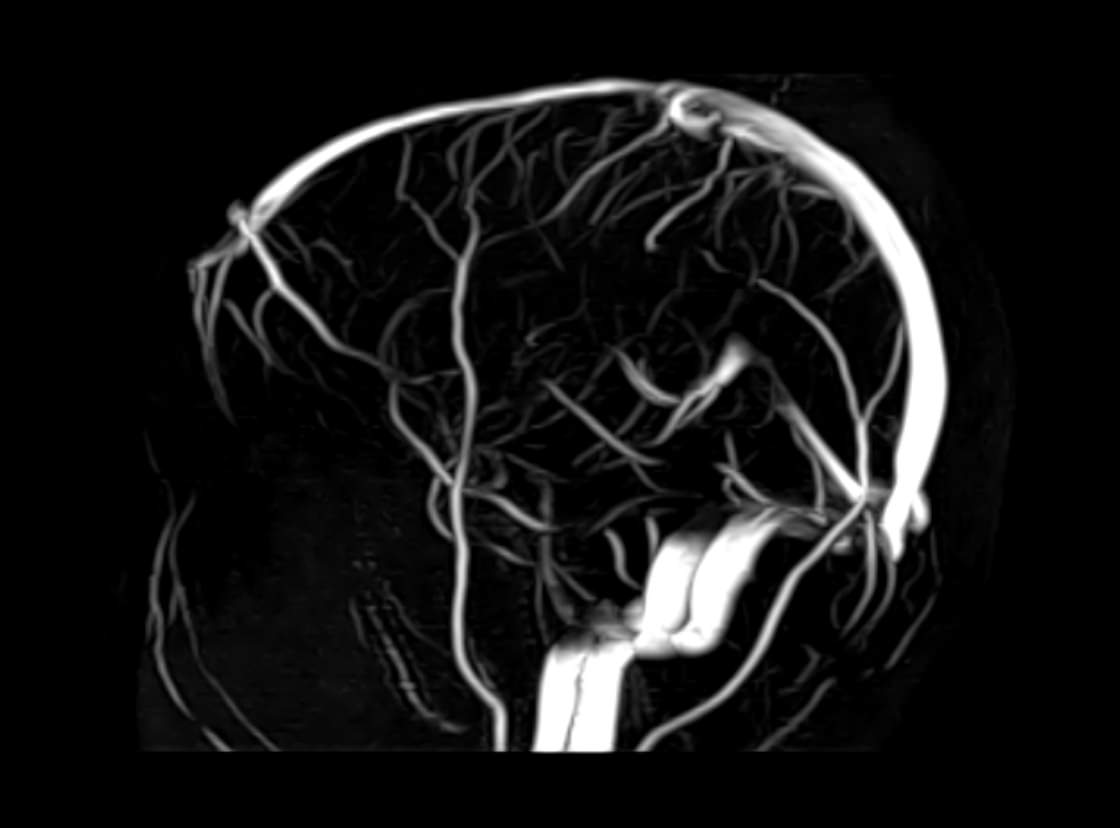

МРТ головного мозга является высокоинформативным методом исследования центральной нервной системы, который дает возможность оценить состояние всех структур головного мозга и поставить правильный диагноз. Стандартную МРТ головного мозга дополняет МР-венография, которая позволяет получить детальную картину строения и функционального состояния венозной системы мозга.

В клинике «Доступная медицина» проводится МРТ головного мозга и МР-венография головного мозга на современном аппарате TOSHIBA VANTAGE TITAN 1,5 Тесла, который обладает высокой чувствительностью и соответствует всем мировым стандартам качества диагностики. Напряженность магнитного поля 1,5 Тесла обеспечивает высокую четкость изображения и позволяет выявлять заболевания на ранних стадиях развития. Процедура МРТ безопасна, так как томограф не испускает рентгеновского излучения, полностью безболезненна и имеет доступную стоимость.

• участки сужения, извитость, образование петель и перегибов сосудов;

• нарушения оттока крови за счет тромбообразования в венозном русле;

• ангиомы, сосудистые мальформации.